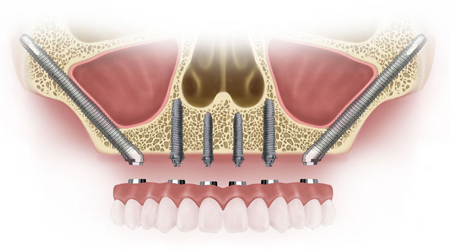

ALL- ON -4 FOR LESS BONE

Upper Jaw/Lower Jaw (Per Jaw)

Technique INR US

4 NOBEL BIOCARE Implants including 2 ANGULATED Implants + IMMEDIATE Provisional Denture + Final Fixed Titanium Hybrid Denture of 12-14 Teeth 350000 5400

4 NOBEL BIOCARE Implants including 2 ANGULATED Implants + IMMEDIATE Provisional Denture + Final Fixed PROCERA Implant Bridge Denture of 12-14 ZIRCONIA Ceramic Crown 500000 7600

ALL- ON -4 WITH ZYGOMA IMPLANTS (FOR MINIMAL BONE)

Upper Jaw

4 NOBEL BIOCARE Implants including 2 ZYGOMA Implants + IMMEDIATE Provisional Denture + Final Fixed TITANIUM HYBRID Denture of 12-14 Teeth 650000 10000

4 NOBEL BIOCARE Implants (QUAD ZYGOMA)+ IMMEDIATE Provisional Denture + Final Fixed TITANIUM HYBRID Denture of 12-14 Teeth 800000 12300

SINUS LIFT PROCEDURE

Indirect 22000 350

Direct SINUS LIFT Procedure 50000 775